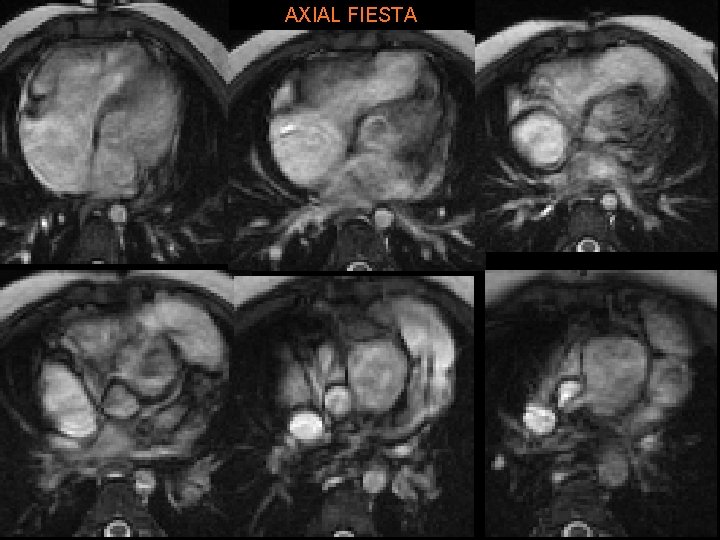

AXIAL FIESTA

A. R. • Treated with modified Norwood & Rastelli procedure: § Conduit from RV to pulmonary artery (w/AV) § Large baffle across VSD from LV to “neoaorta” • Constructed from Ao arch, descending Ao, MPA. • Ao root is anastomosed to neoaorta. • “Systemic valve” is PV § Closure of ASD § Repair of coarct.